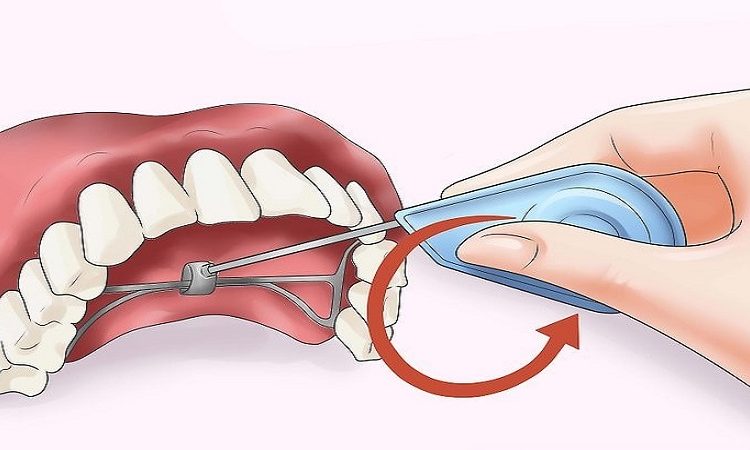

نحوه نصب و نگهداری بزرگ کننده فک بزرگ کننده فک به دلیل کاربردهای گوناگون، درمان با این دستگاه در بیماران مختلف متفاوت است. چون اکسپندر متناسب با شکل دهان هربیمار و به صورت سفارشی ساخته میشود، حداقل دو نوبت ویزیت لازم است: یکی برای برداشتن قالبگیری از دهان و دیگری (یکی-دوهفته بعد) برای قرار دادن